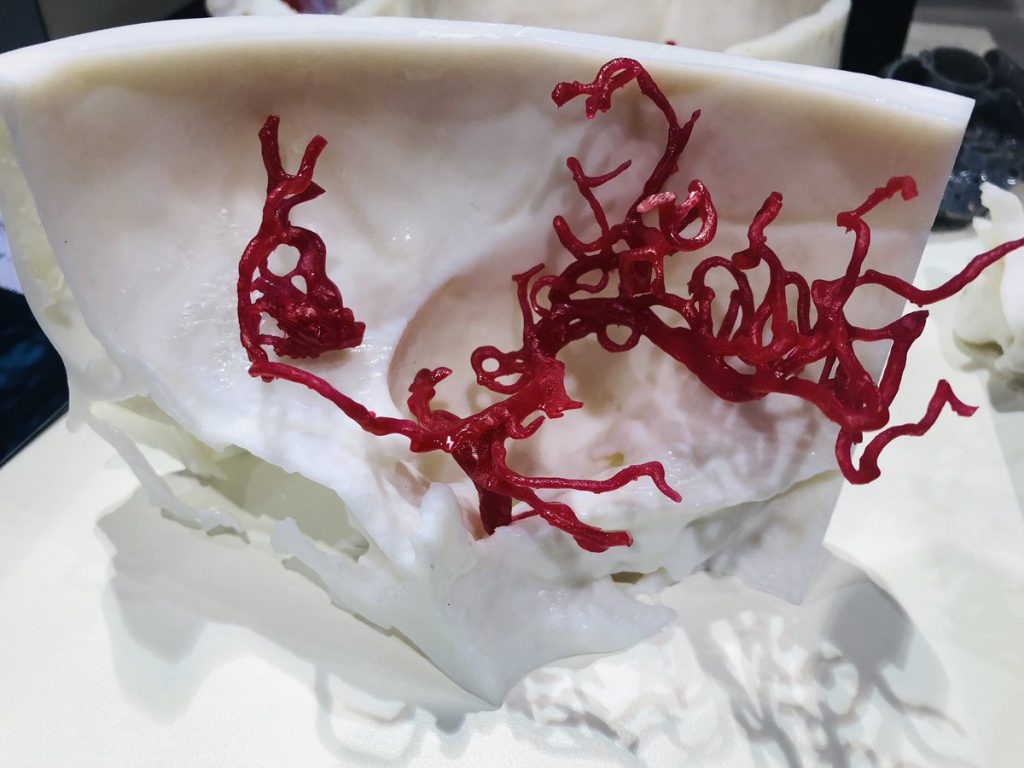

axial3D, a medical manufacturing service provider headquartered in Northern Ireland, is providing Newcastle Hospitals NHS Foundation Trust with an on-site 3D printing lab. Housed at the Royal Victoria Infirmary, one of six potential beneficiaries of the facility, the lab will be used to produced patient-specific models for pre-surgical planning.